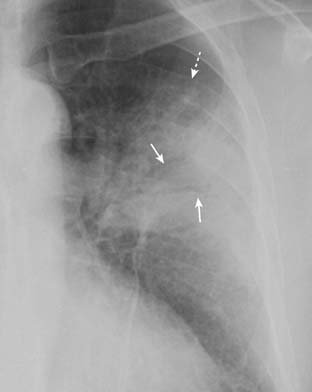

Figure 7-8 Post-primary tuberculosis (reactivation tuberculosis).

A cavitary pneumonia is present in both upper lobes (solid white arrows). Numerous lucencies (cavities) are seen throughout the airspace disease in the right upper lobe (solid black arrows). A cavitary upper lobe pneumonia is presumptively TB, until proven otherwise. In addition, airspace disease is seen in the lingula (dashed white arrow), another finding suggestive of TB, a disease which can spread via a transbronchial route to the opposite lower lobe or another lobe in the lung.